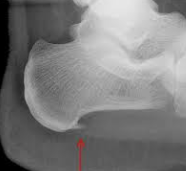

骨瘤の発生部位によって、内側管骨瘤(medial splints)、外側管骨瘤(lateral splints)、後管骨瘤(posterior splints)、深管骨瘤(deep splintts)に分けられますが、他に外傷性管骨瘤(traumatic splints)が発生する。

管骨内側の上1/3の部分において、大中手骨と内側小中手骨との間に生じます。これは大中手骨と内側小中手骨とをつなぐ、中手骨列内靭帯(腕前骨間靭帯)が不断に機械的刺激を受けて炎症をおこし、ついで骨膜に波及して骨化性骨膜炎から骨瘤を形成したものです。

このほか、第Ⅱ中手骨の後角に生ずる後管骨瘤と、第Ⅲ中手骨の上端後面の繋靱帯起始部に生ずる深管骨瘤は、いずれも靭帯、腱および筋膜などの緊張牽引により、その付着部の骨膜に骨化性骨膜炎をおこして発するものです。